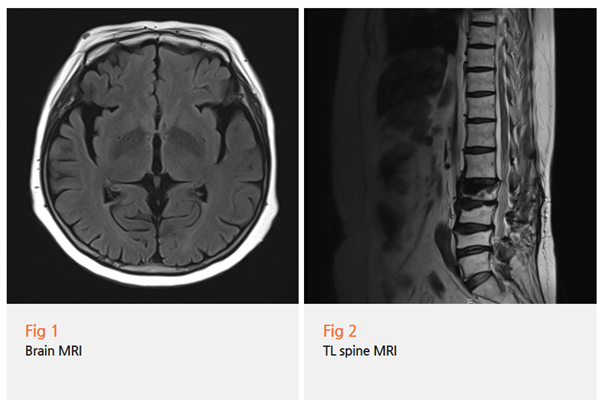

뇌 MRI, MRA 다 찍어봤는데 별 이상 없다고 하고,

손떨림 약도 먹어봤는데 별로 효과가 없었다고...

✔️ 단순 검사만으로 판단하는 경우

MRI나 혈액검사만으로는 파킨슨병을 진단하기 어려워요.

임상 증상과 경과를 종합적으로 봐야 하는데,

시간이 부족하다 보니 놓치는 경우가 있죠.